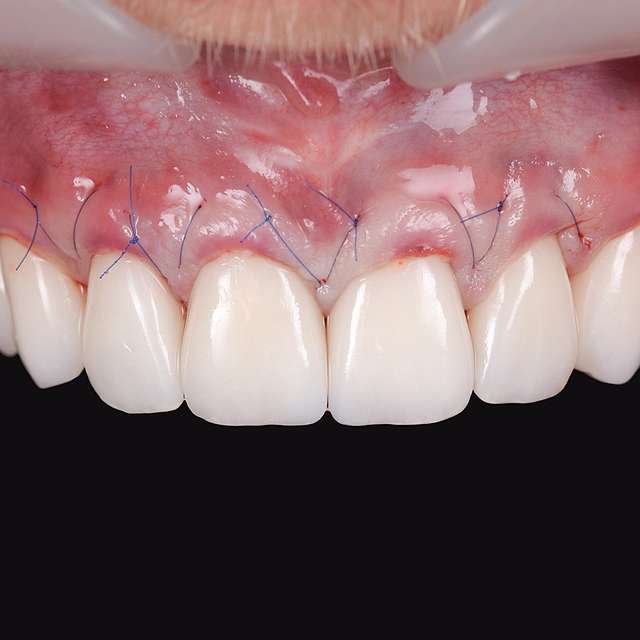

Grefa gingivala este o micro-chirurgie prin care se transplanteaza o mica bucata de tesut moale - gingie sau tesut conjuctiv (stratul intern al gingiei) pentru a acoperi un defect gingival. De obicei, acest tip de interventie este necesar pentru augmentarea implanturilor dentare, sau pentru a acoperi defecte cauzate de traume sau de afectiuni parodontale.Grefele se recolteaza din zona molarului de minte, sau de pe palat, si sunt transplantate in zona afectata.

Acesta interventie este una foarte delicata, lamele folosite pentru a efectua procedura sunt aceleasi folosite in oftalmologie, iar firele de sutura sunt si ele foarte fine. Firele se indeparteaza dupa 7-14 zile, in functie de caz, cand are loc vindecarea primara. Maturarea grefei dureaza aproximativ 90 zile, de aceea in momentul inserarii implanturilor preferam sa facem si grefa de tesut, pentru a sincroniza timpii de vindecare si ambelor proceduri.